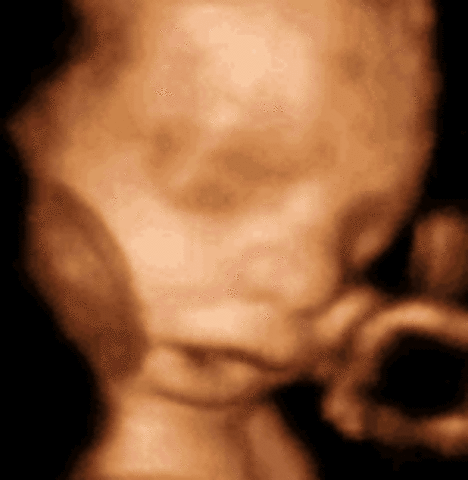

• week 12

week 12

The most dramatic development this week: reflexes. Your baby's fingers will soon begin to open and close, his toes will curl, his eye muscles will clench, and his mouth will make sucking movements. In fact, if you prod your abdomen, your baby will squirm in response, although you won't be able to feel it. His intestines, which have grown so fast that they protrude into the umbilical cord, will start to move into his abdominal cavity about now, and his kidneys will begin excreting urine into his